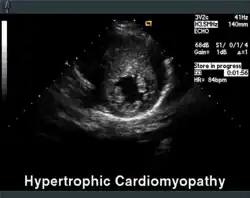

Die Echokardiographie ist das diagnostische Mittel der Wahl. Neben der Septumhypertrophie (> 15 mm) kann hier häufig auch ein verlagertes Mitralklappensegel gesehen werden, welches in der Systole eine Bewegung zum Septum macht und den Ausflusstrakt zusätzlich einengt (systolic anterior movement = SAM). Im Weiteren können der Ruhe-Gradient im linksventrikulären Ausflusstrakt (LVOT), d. h. ein Drucksprung zwischen linker Herzkammer und Hauptschlagader, gemessen sowie die Herzmuskelversteifung beurteilt werden.